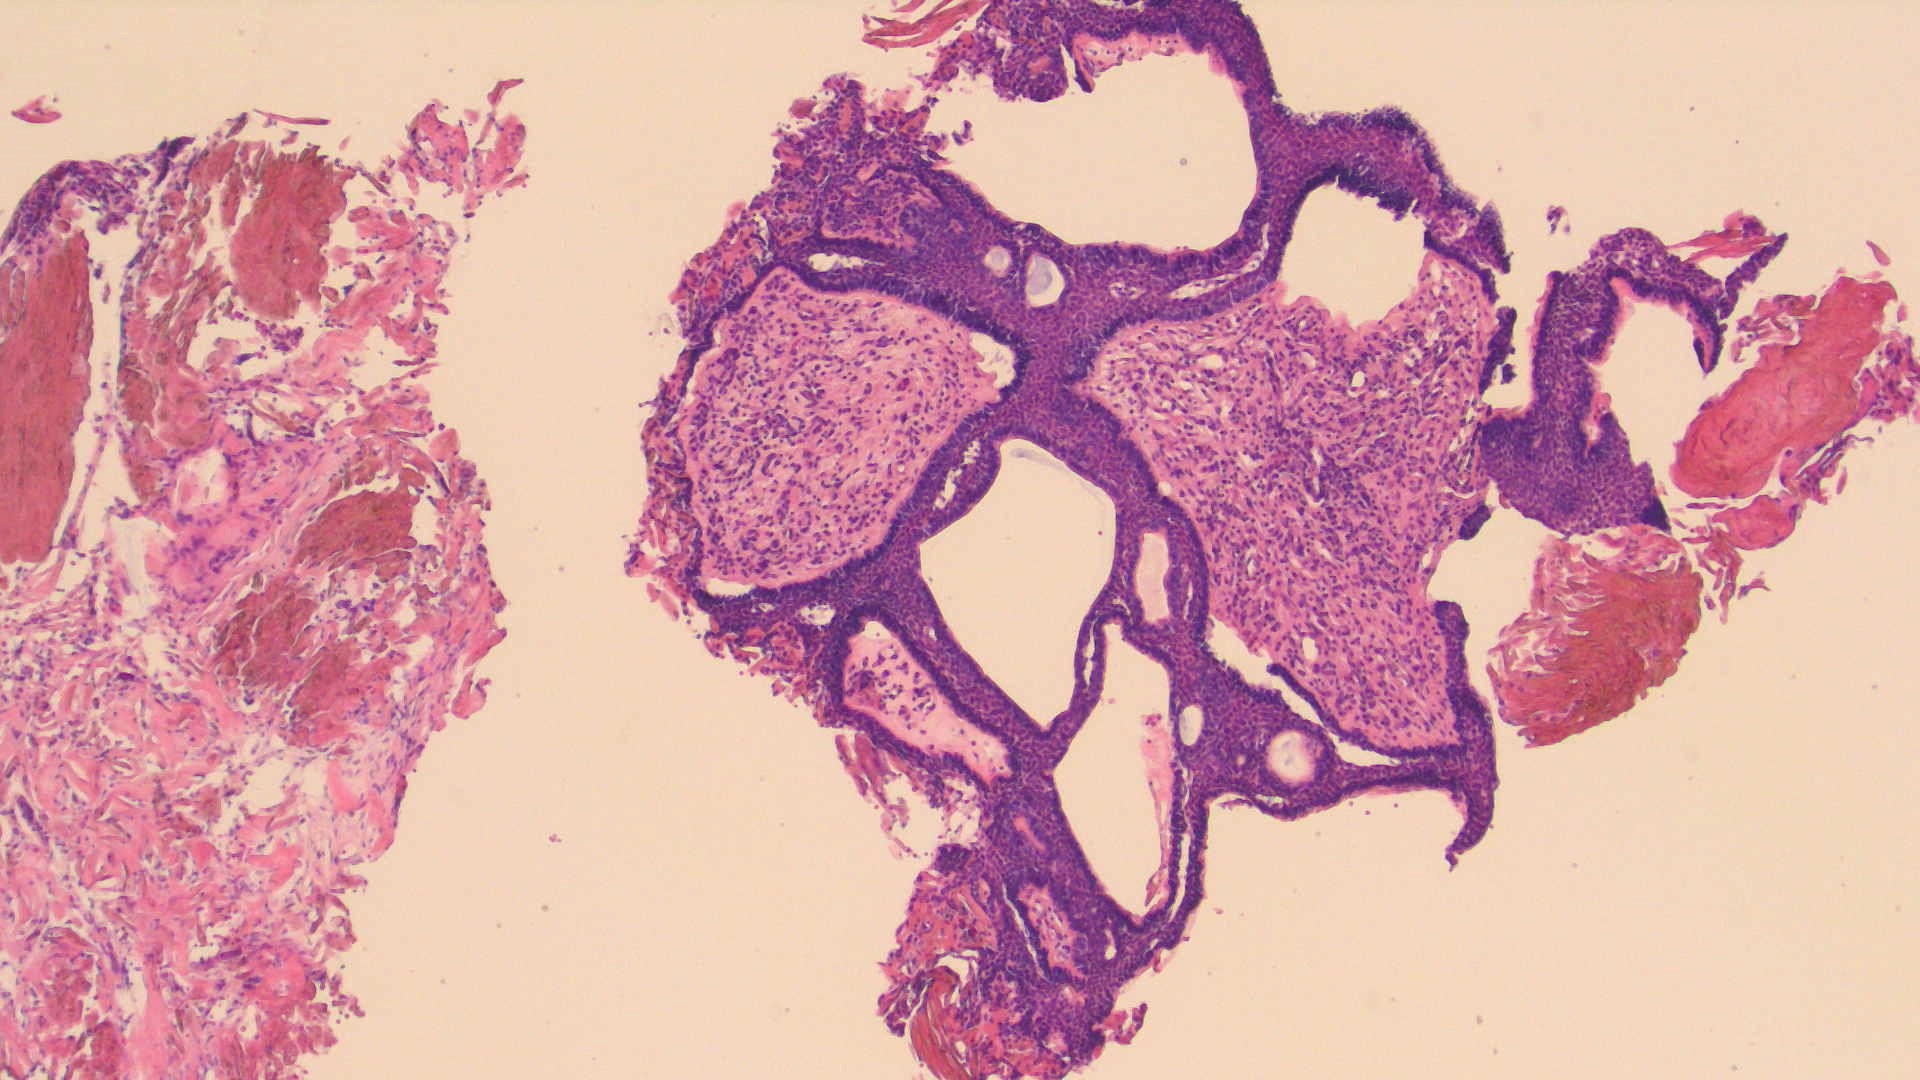

Dx: Adamantinomatous craniopharyngioma, WHO Grade 1

-Aggressive clinical course - invasive and recurrent

-Post-op complications can include chemical meningitis from keratin spillage into the CSF and diabetes insipidus from resection of post pituitary. Fragments of post pituitary can be identified with a TTF-1 stain where the glial cells will demonstrate nuclear positivity.

-Molecular: CTNNB part of the WNT pathway nuclear (+) for beta catenin

-3 micro features – wet keratin, basal palisading and loose reticulum